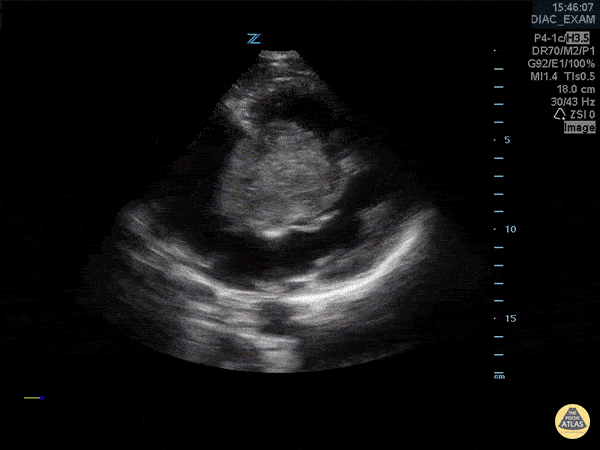

In this parasternal long axis view, a large mass is present in the right atrium that moves into the right ventricle during diastole. Frances Russell, MD, RDMS